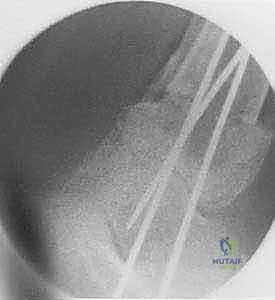

باستخدام أدوات قطع عظمية دقيقة جداً (مناشير جراحية متأرجحة)، وتحت توجيه جهاز الأشعة السينية المباشر في غرفة العمليات (C-arm)، يتم إحداث القطع في عظم الظنبوب في المكان المخطط له مسبقاً، مع الحفاظ على جزء بسيط من القشرة العظمية في الجهة المقابلة لتعمل كمفصلة (Hinge).

5. التثبيت الصلب وزراعة الطعم العظمي

في حالة "فتح الإسفين"، يتم وضع طعم عظمي (يؤخذ غالباً من عظم الحوض للمريض أو طعم صناعي متقدم) لملء الفراغ. بعد ذلك، يقوم الدكتور هطيف بتثبيت العظم في وضعه الجديد القويم باستخدام شرائح معدنية تشريحية مصممة خصيصاً لهذه المنطقة (Anatomical Locking Plates) ومسامير قوية. هذا التثبيت الصلب يضمن التئام العظم بشكل صحيح.